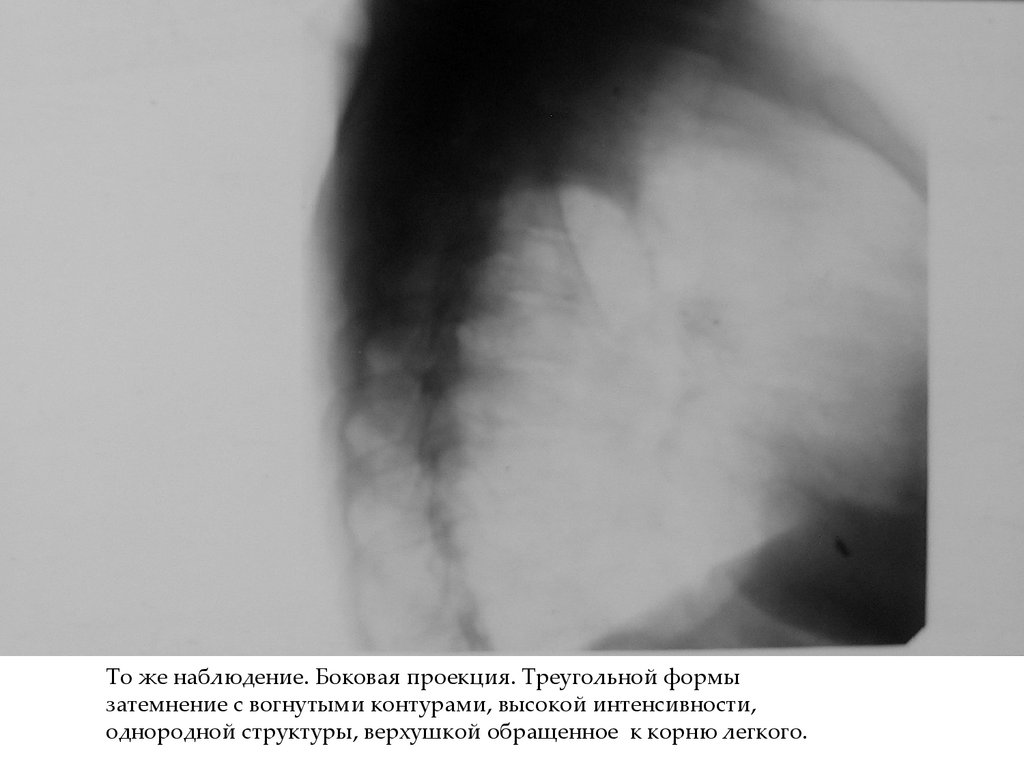

То же наблюдение. Боковая проекция. Треугольной формы

затемнение с вогнутыми контурами, высокой интенсивности,

однородной структуры, верхушкой обращенное к корню легкого.